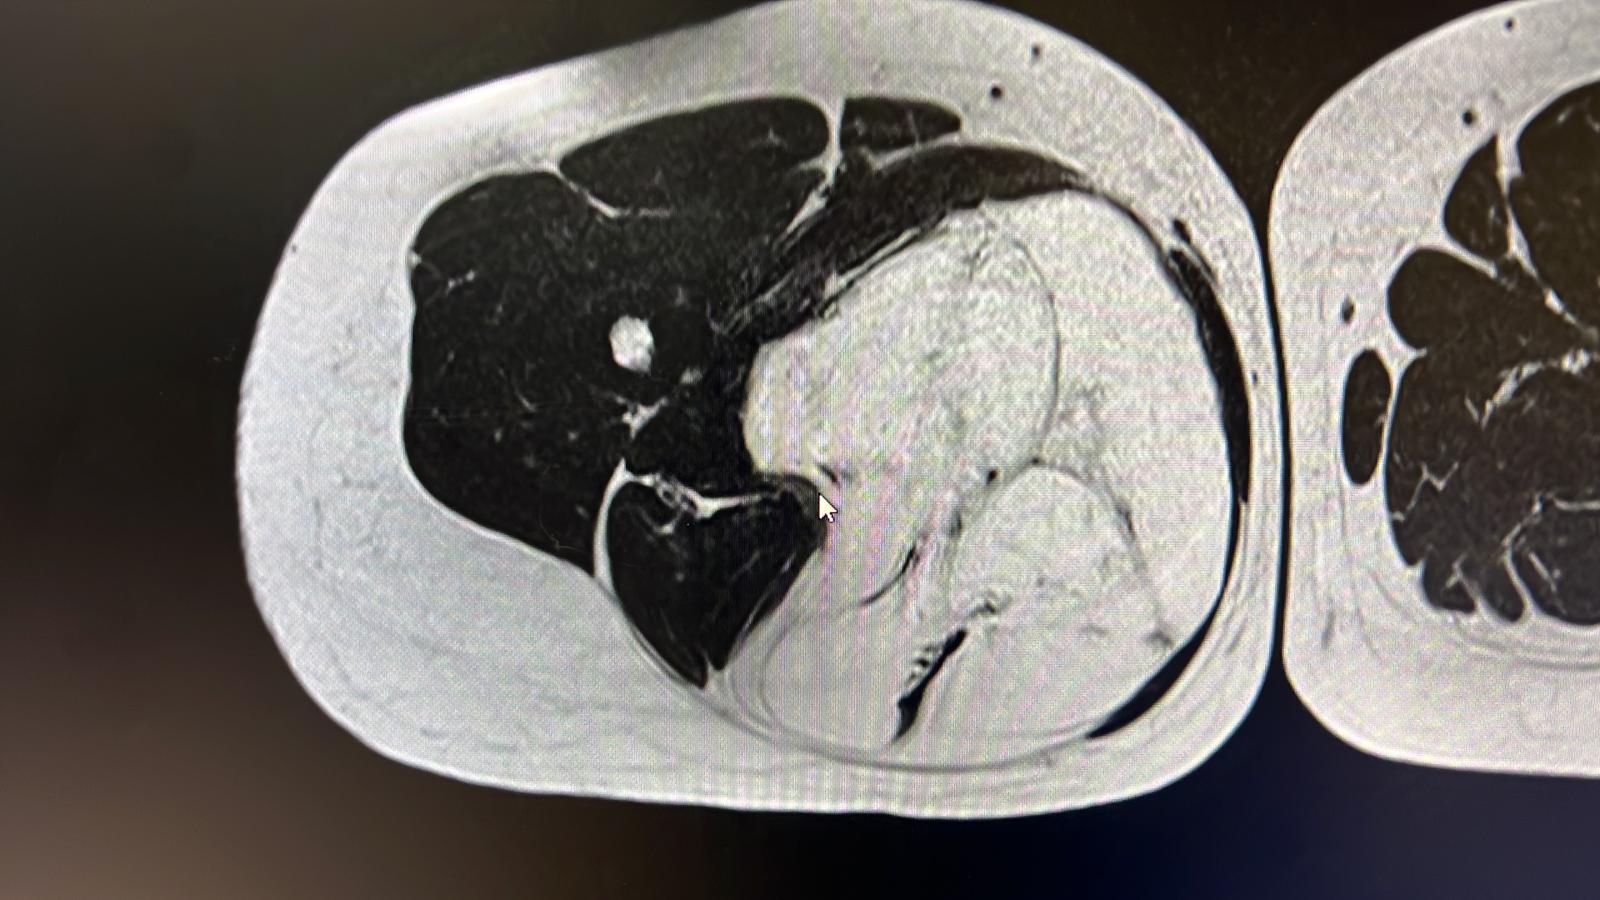

El liposarcoma es un tipo de cáncer que se origina a partir del tejido graso del cuerpo.

Se trata de un subtipo de sarcoma que se desarrolla en los tejidos blandos, comúnmente dentro de los músculos, entre los músculos, en el tejido celular subcutáneo y en el retroperitoneo.

Se produce cuando las células del tejido graso experimentan cambios anormales y comienzan a crecer de manera descontrolada. Puede desarrollarse en cualquier parte del cuerpo que contenga tejido graso, pero es más común en las extremidades, especialmente en los muslos y las piernas. También puede afectar otras áreas, como el abdomen y los tejidos retroperitoneales (ubicados detrás del abdomen).